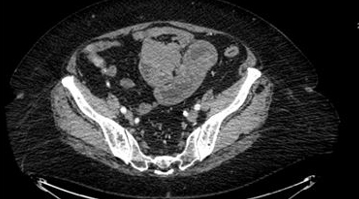

A computed tomography (CT) imaging of the abdomen and pelvis with intravenous contrast was obtained (Figure 1). The radiologist communicated concern for a solid mass measuring 5 × 5 cm in the left mid-abdomen or the pelvis causing a proximal small bowel obstruction.

Figure 1: CT abdomen/pelvis with IV contrast demonstrating mass-like lesion with associated bowel obstruction.